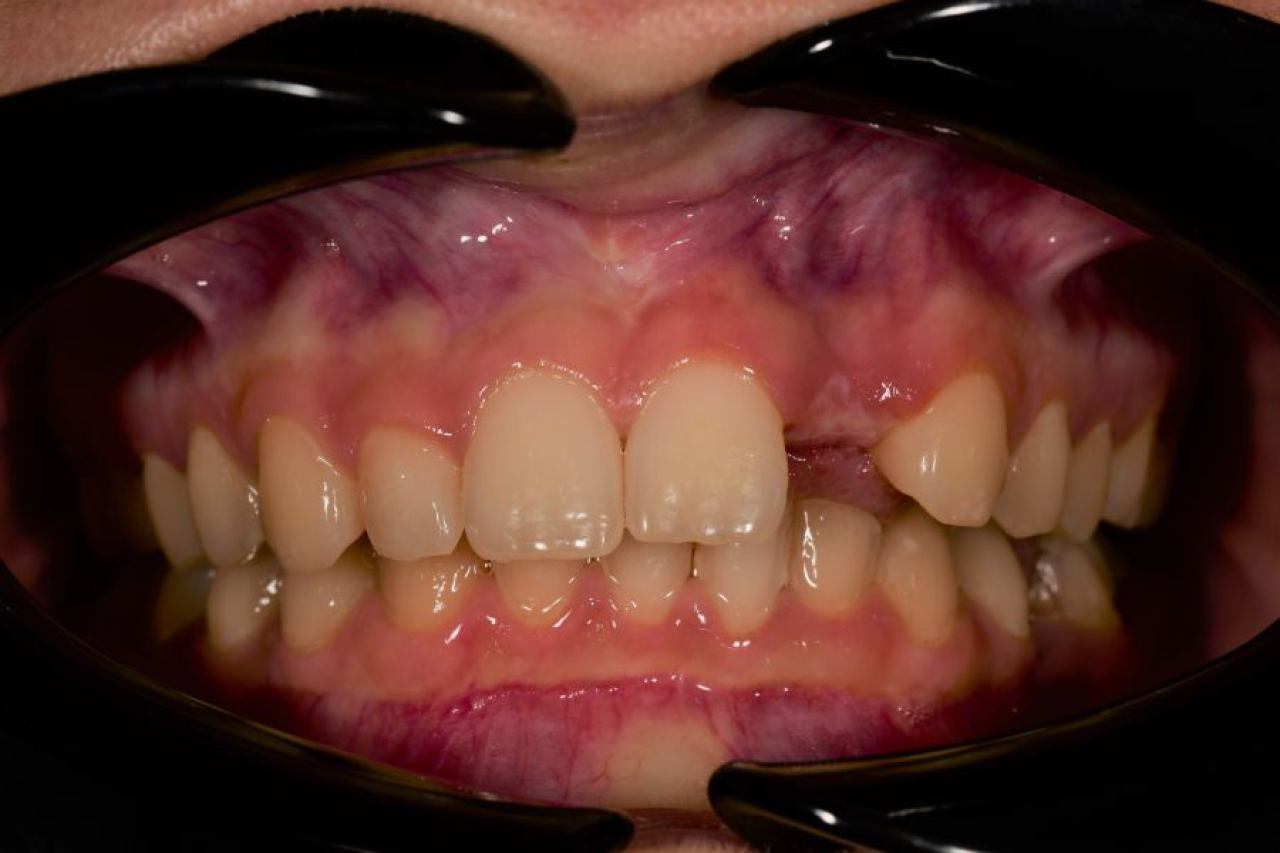

Parodontologija i kirurgija

Parodontologija je grana dentalne medicine koja se bavi zdravljem potpornih struktura zuba (parodonta). Parodont se sastoji od zubnog mesa (gingiva), kosti i vlakana koja vežu zub za kost (parodontalni ligament).

Ovo je grana kojoj Marković Dental Clinic pridaje puno pažnje jer je vrlo kompleksna i bitna za cijelo oralno zdravlje.